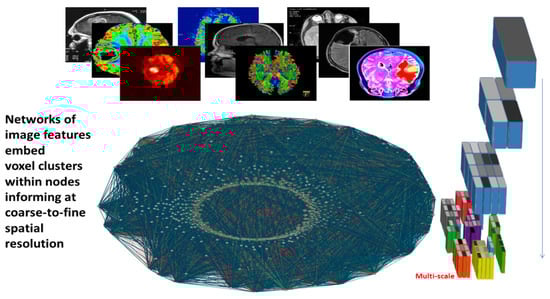

Networks are well-suited mathematical representations of complex data derived at different scales, as they engage nodes and links to quantify measurements in their evolving dynamics (Figure 3).

Figure 3. Multiscale information network processing from image features.